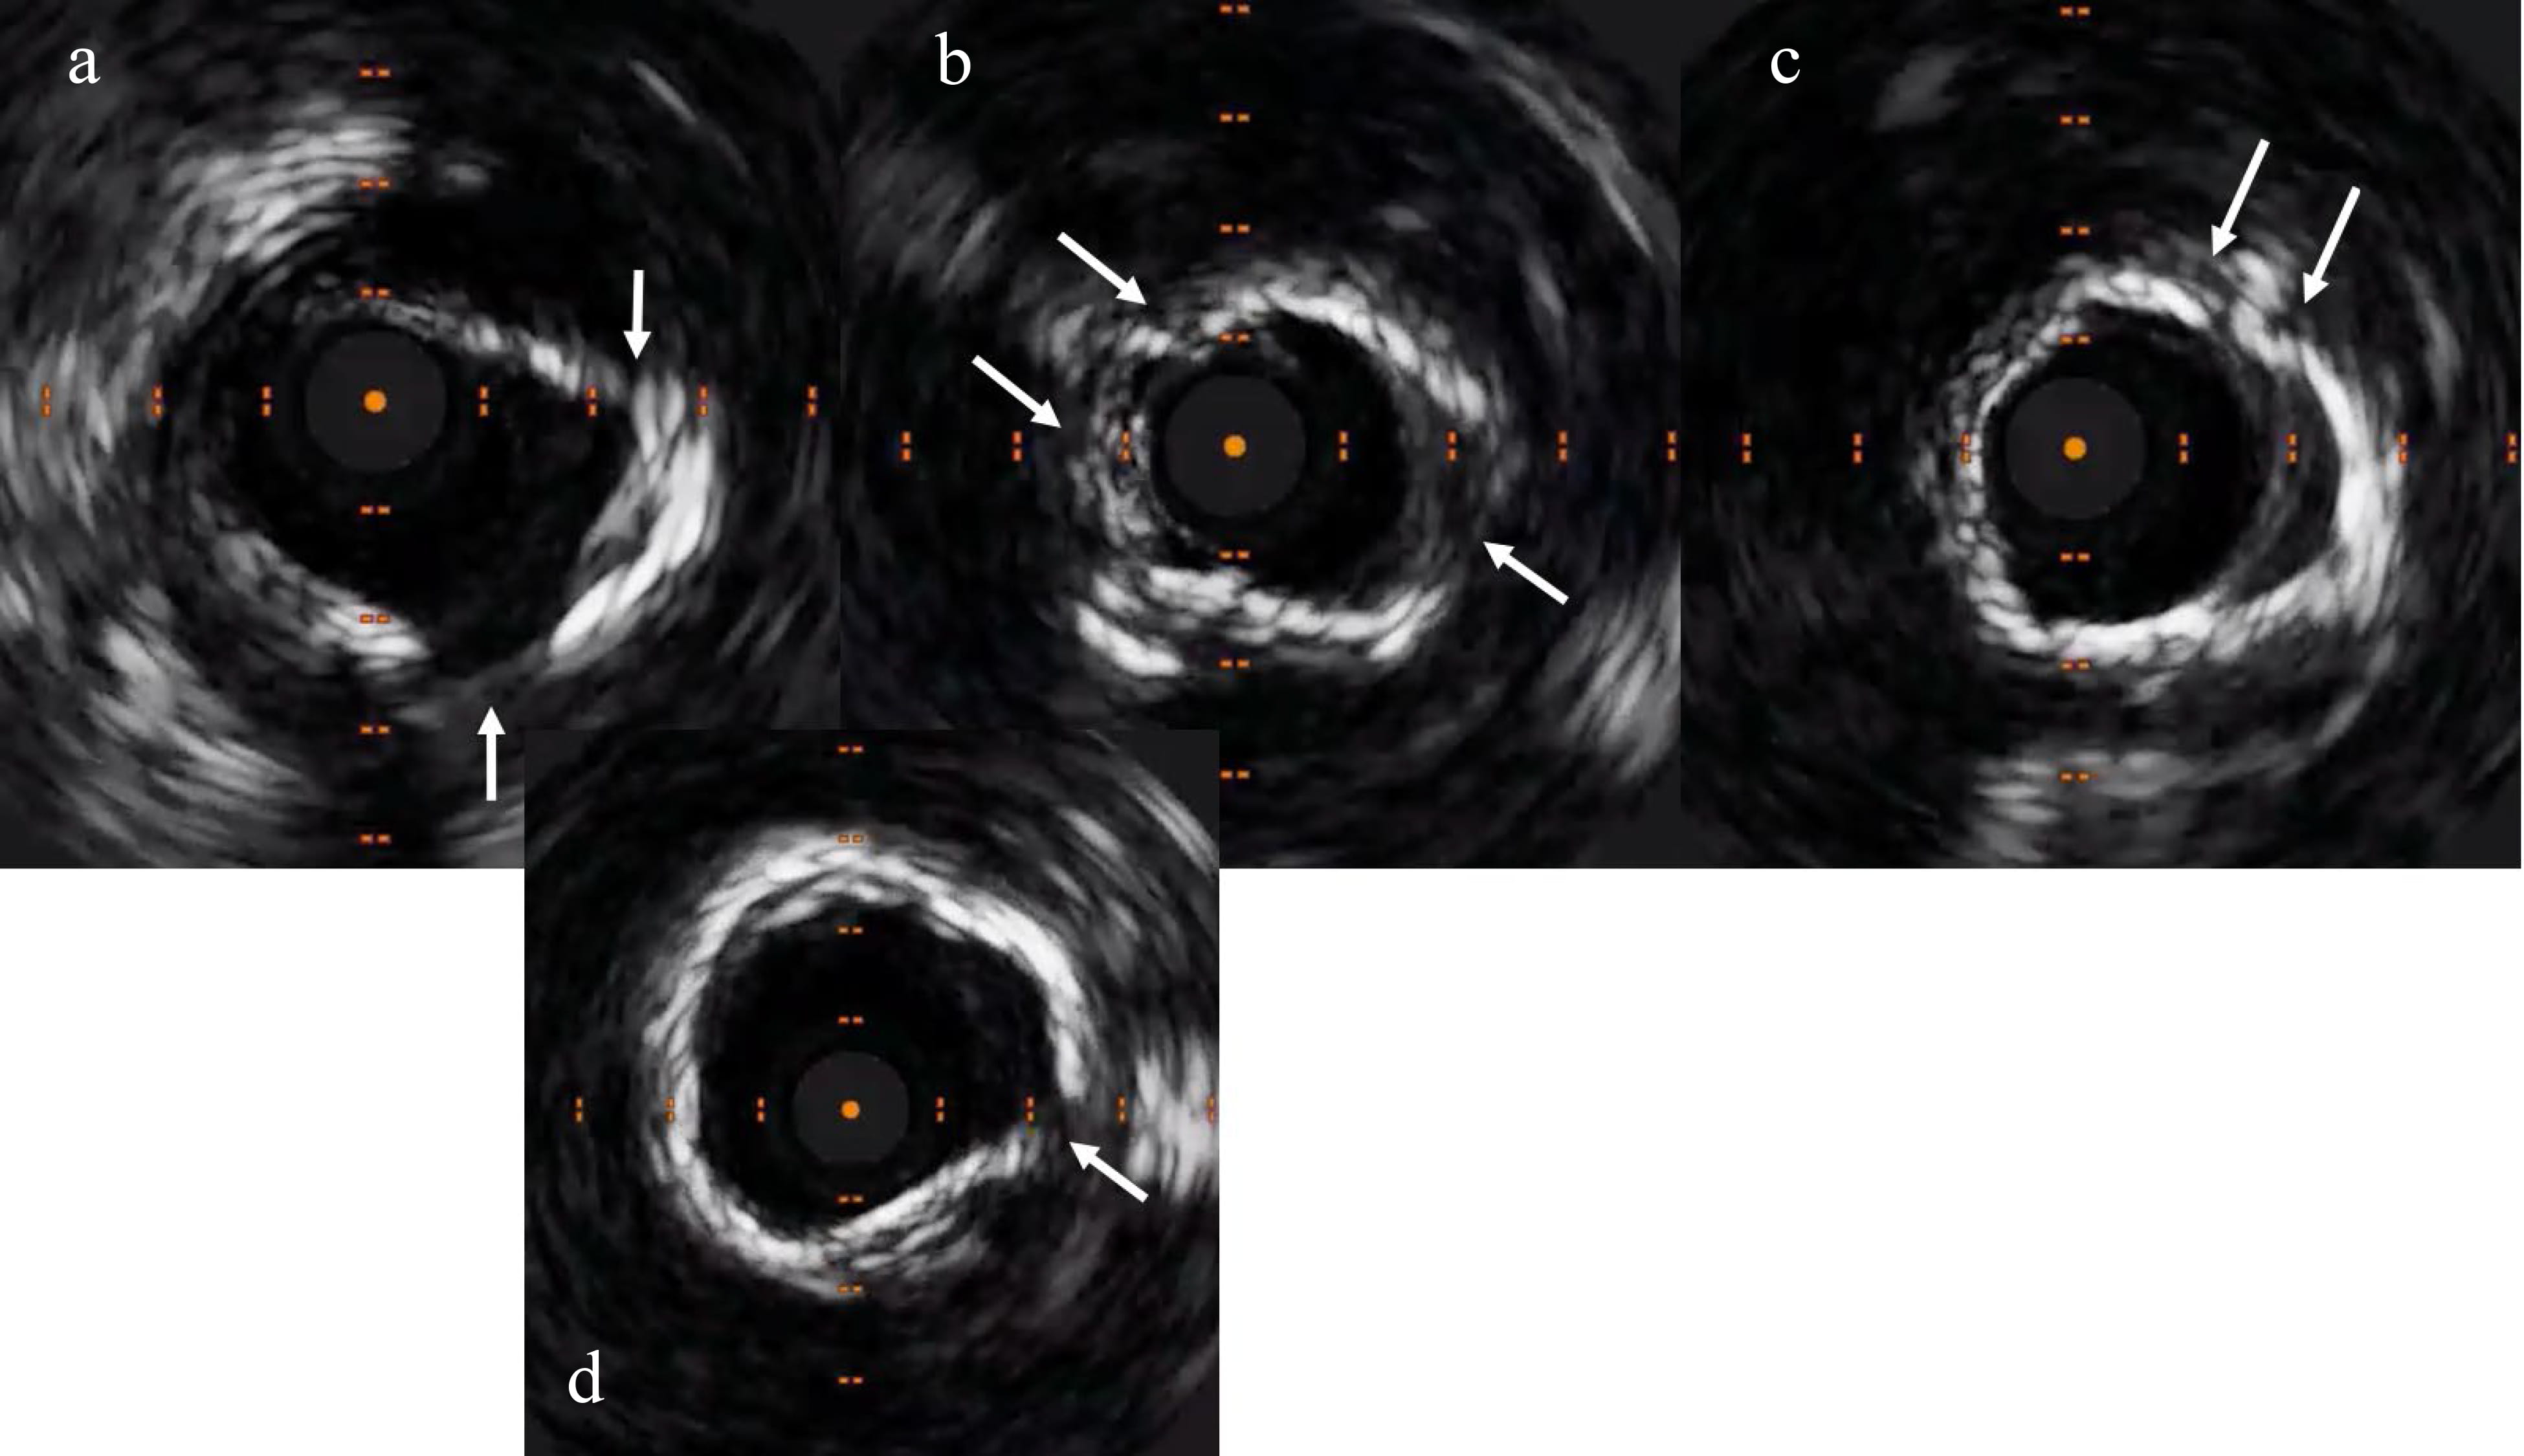

resulted in bursting of a 3.5 mm non-compliant balloon (Fig. 3). Intravascular

imaging visualised concentric calcium (Fig. 4). Subsequently, we used a 3.5 mm

Fig. 3.IVUS exhibiting concentric calcification at the site of lesion, which was not yielding. (a) Calcium arc extending from 9’o clock to 5’o clock positions (shown by the arrows). (b) Calcium arc extending from 1’o clock to 6’o clock positions (shown by the arrows).

Fig. 5.Repeat IVUS exhibiting crack in the calcium (shown by the arrows). (a) Cracks at 2 and 5’o clock positions. (b) Cracks at 4 and 10’o clock positions. (c) Crack at 1’o clock position. (d) Crack at 3’o clock position (shown by the arrows).